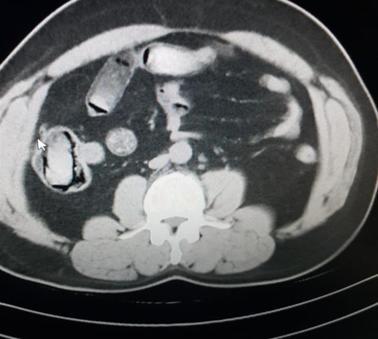

Police released X-ray images of the unidentified suspects, who arrived in Turkey from Iran last week, showing a total of 298 capsules they had swallowed filled with nearly 3.4 kilograms (almost 7.5 pounds) of heroin.

Nothing was found until they were made to undergo an X-ray scan that revealed hundreds of capsules in their stomachs.